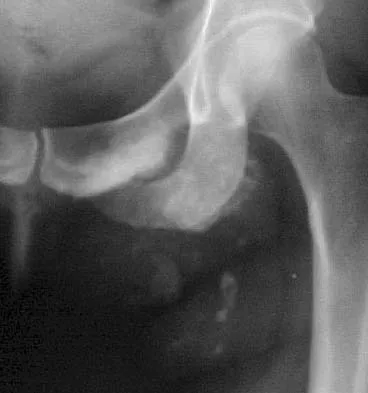

A 21-year-old collegiate female cross-country athlete reports right hip pain that begins about 12 miles into a run, followed by pain resolution when she discontinues running. However, each time she tries to resume a running program, she experiences recurrence of pain deep in the anterior groin. A plain radiograph and MRI scan are shown in Figures 8a and 8b. Management should consist of

Explanation

The history is consistent with a stress fracture. Findings on the plain radiograph are marginal, but the MRI scan shows evidence of stress reaction in the medial neck of the femur (compression side). A lesion on the compression side is not normally at risk for displacement and usually can be managed nonsurgically. A bone scan would further identify the lesion but is not necessary. A skeletal survey and chest radiograph are used in staging a tumor. Radioisotope injection and guided biopsy are sometimes used for osteoid osteomas. Boden BP, Osbahr DC: High-risk stress fractures: Evaluation and treatment. J Am Acad Orthop Surg 2000;8:344-353.